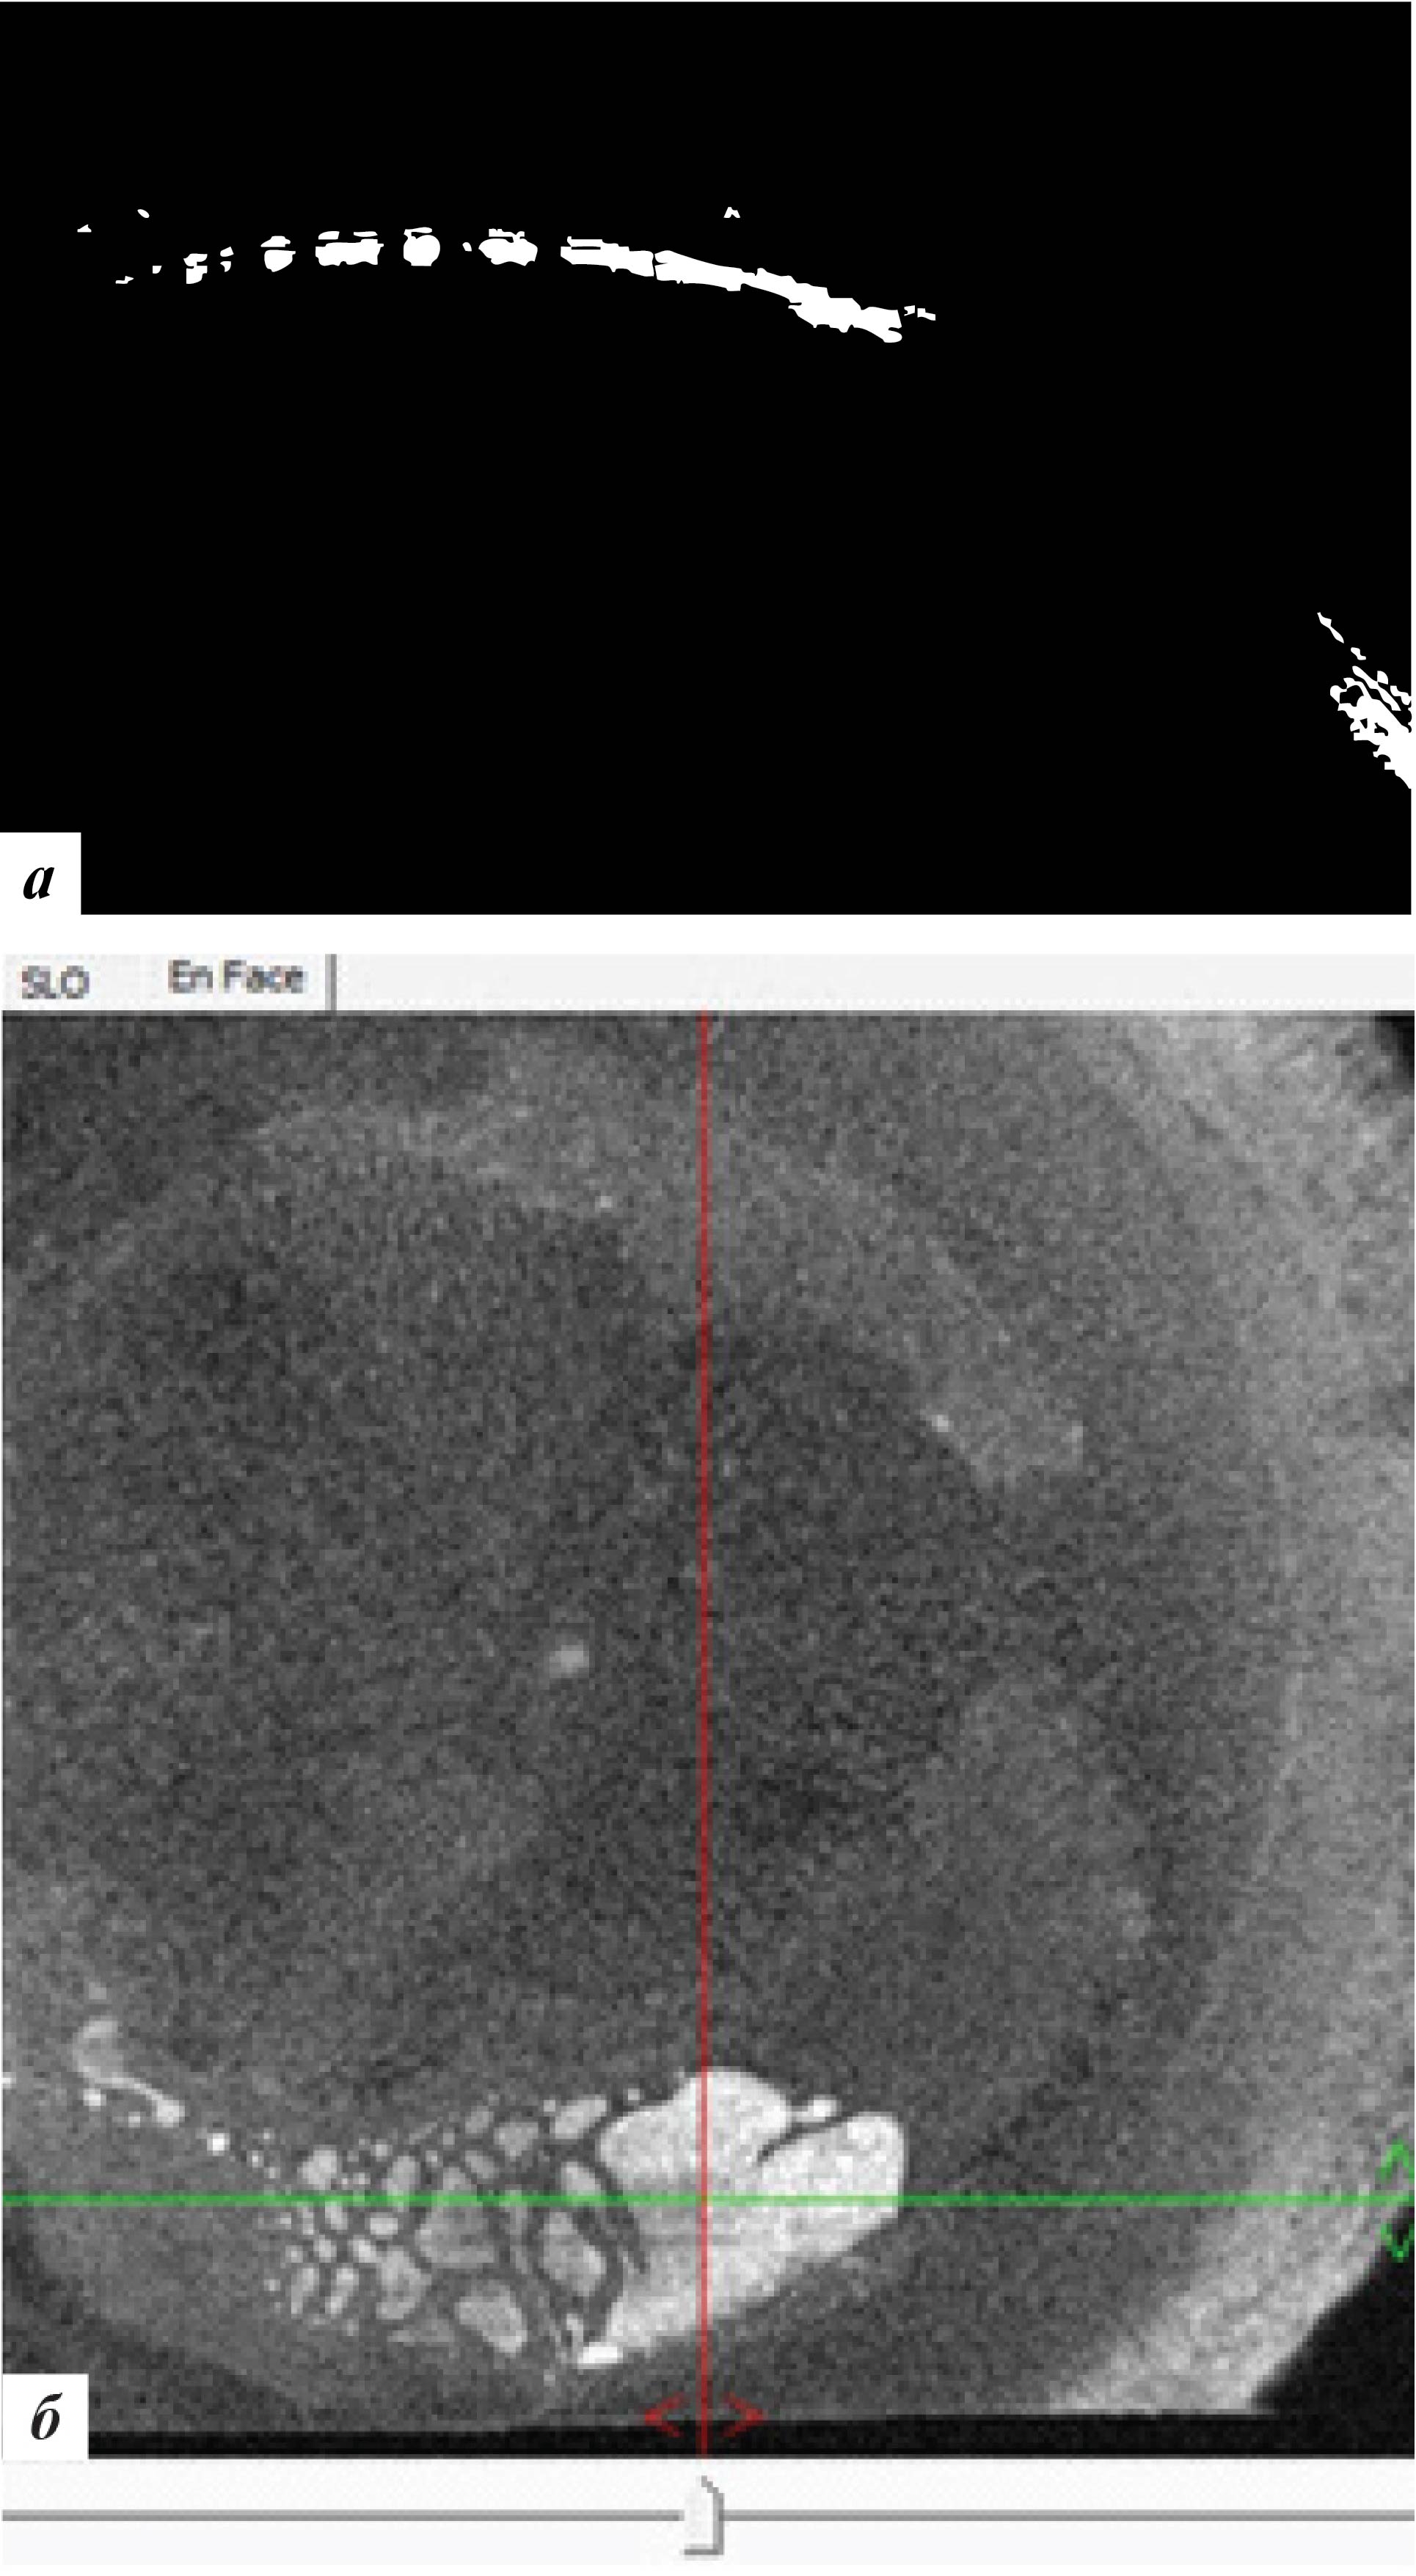

Высота вросшего эпителия по данным ОКТ роговицы уменьшилась (рис. 7). Пациентке было рекомендовано продолжение наблюдения.

Рис. 7. Данные ОКТ роговицы левого глаза через 3 месяца после лечения: а – горизонтальная проекция, б – фронтальная проекция

При офтальмобиомикроскопии глаз спокоен, в роговичном интерфейсе в ЦОЗ и параоптической зоне отмечена элиминация эпителиальных клеток с формированием стойких облаковидных помутнений (рис. 8) с отсутствием перифокального отека. ОКТ-сканирование передней поверхности роговицы также подтвердило отсутствие признаков рецидива врастания (рис. 9). С рекомендациями использования слезозаменителей пациентка выписана по месту жительства.

Рис. 9. Данные ОКТ роговицы левого глаза через 9 месяцев после лечения: а – горизонтальная проекция, б – фронтальная проекция